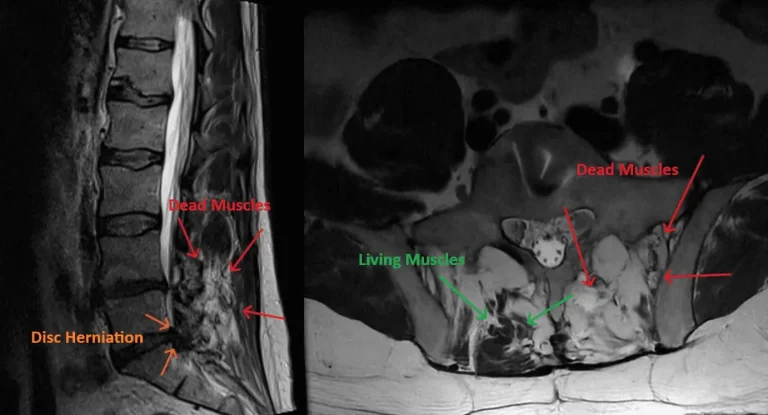

MRI of lumbar spine showing recurrent disc herniation post discectomy highlighted by arrows.

Recurrent Herniation